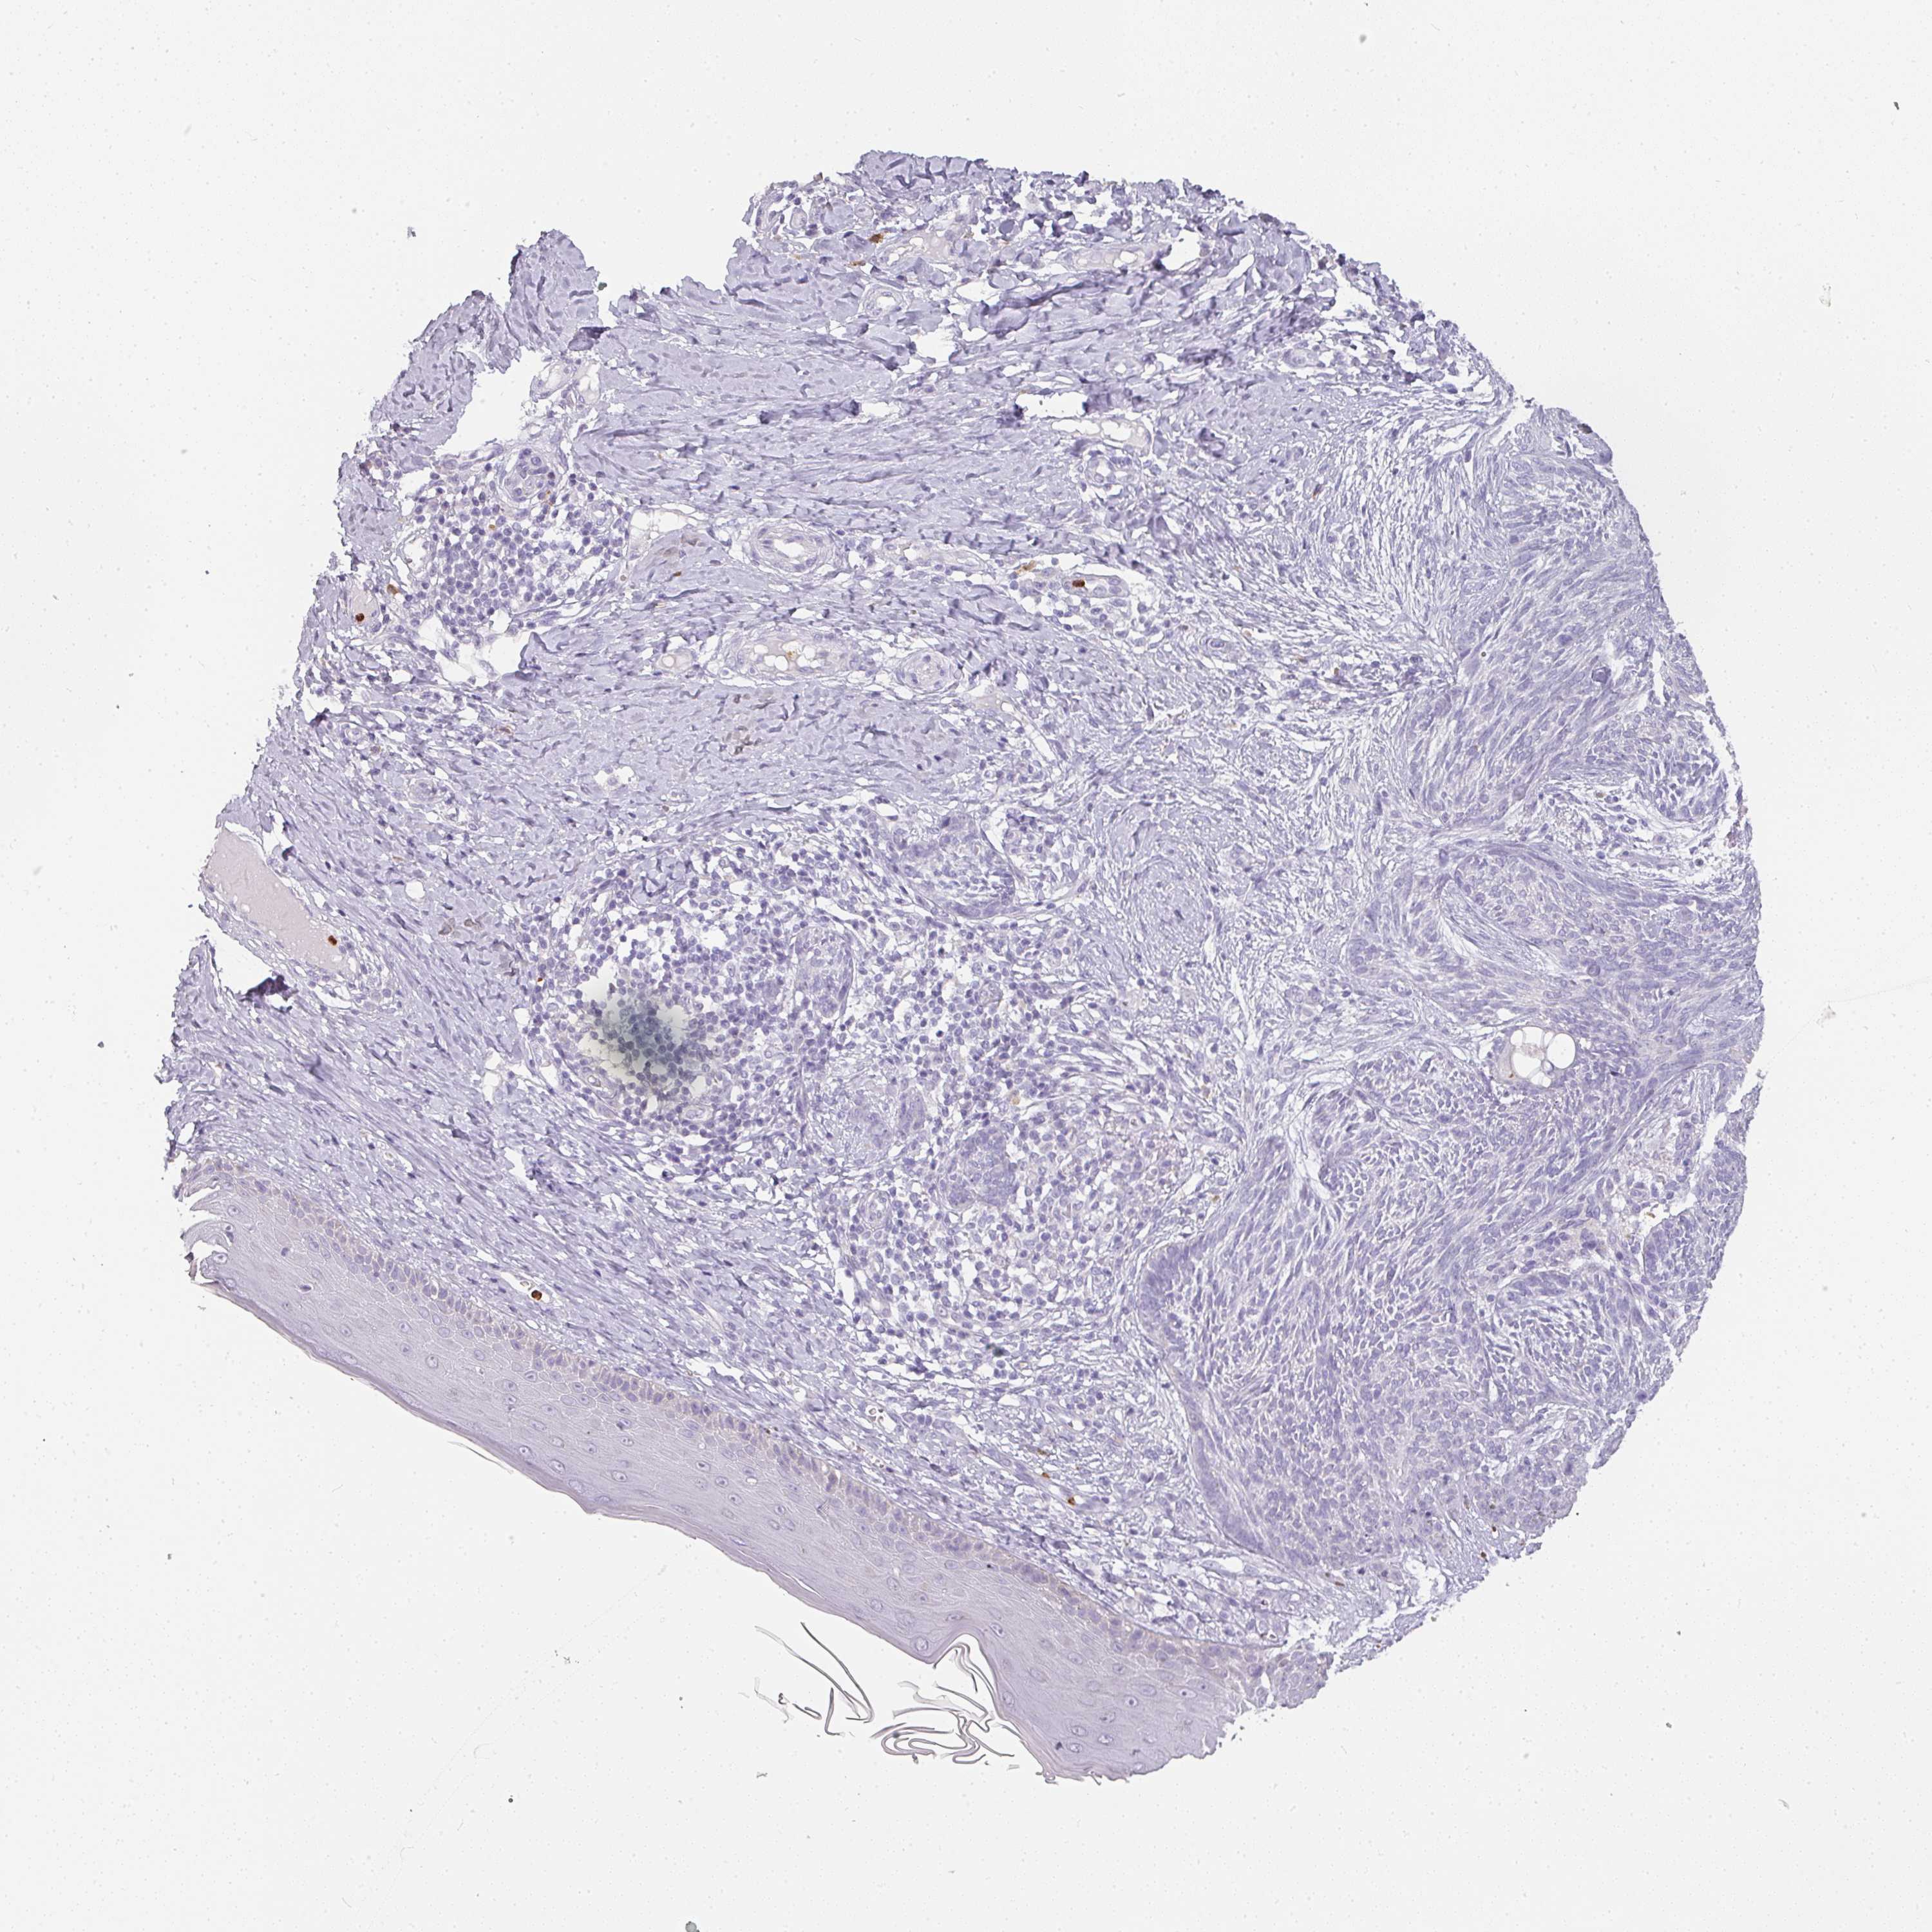

SKIN CANCER - Protein expressioni

A mouse-over function shows sample information and annotation data. Click on an image to view it in a full screen mode. Samples can be filtered based on level of antibody staining by selecting one or several of the following categories: high, medium, low and not detected. The assay and annotation is described here.

Antibody staining in the annotated cell types in the current human tissue is reported as not detected, low, medium, or high, based on conventional immunohistochemistry profiling in selected tissues. This score is based on the combination of the staining intensity and fraction of stained cells.

Each image is clickable and will lead to virtual microscopy that enables deeper exploration of all samples and also displays staining intensity scores, fraction scores and subcellular localization as well as patient and tissue information for each sample.

Basal cell carcinoma